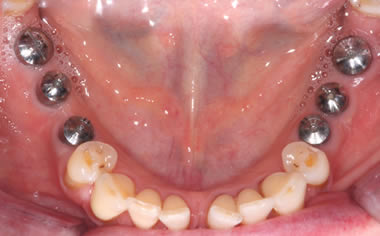

Full arches of teeth replaced by dental implants

Case One (5 images)

Full set of lower teeth fixed onto five dental implants.